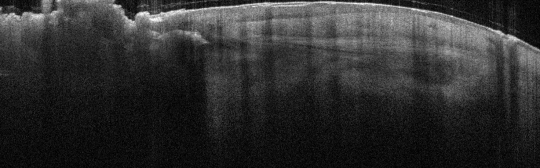

VA15: Right Dorsal Hand, Squamous Cell Carcinoma, Invasive, Keratoacanthoma type

- Arrows indicate extent of squamous mass